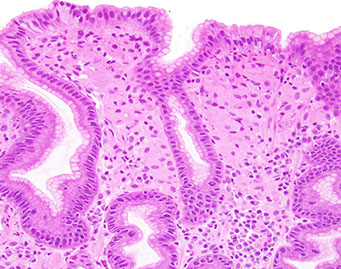

Menetrier's disease

- see Foveolar hyperplasia in hypertrophic gastritis

Gastric hypertrophy w/ protein loss, excessive TGF-a production

- Inc mucous secretion --> protein loss

- clustered incidence in middle-aged men (30-60 yo)

-- Childhood form assoc w/ CMV infection, H pylori in adults

*** hypo-CPG: Chlorine / Protein / Gastrin ***

Precancerous lesion (inc risk gastric cancer)

- Rugae so hypertrophied they look like brain gyri

Micro: parietal cell atrophy, inc mucous cells (lots of mucous production), mucosal cysts, foveolar hyperplasia, glandular atrophy, edematous but uninflamed lamina propria usually limited to body and fundus

IPX (?): TGF-alpha

Tx: supportive

Menetrier disease